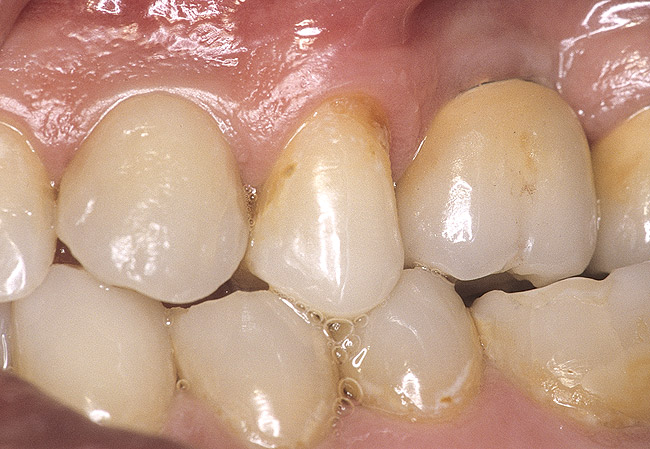

Second-stage surgery was performed after 5 months; healing abutments were placed, and the soft tissue was allowed to heal for an additional 5 weeks. Splinted porcelain-fused-to-metal (PFM) crowns supported by custom gold abutments then were delivered (Figure 5).

Figure 5  Final implant-supported PFM restorations.

Figure 5